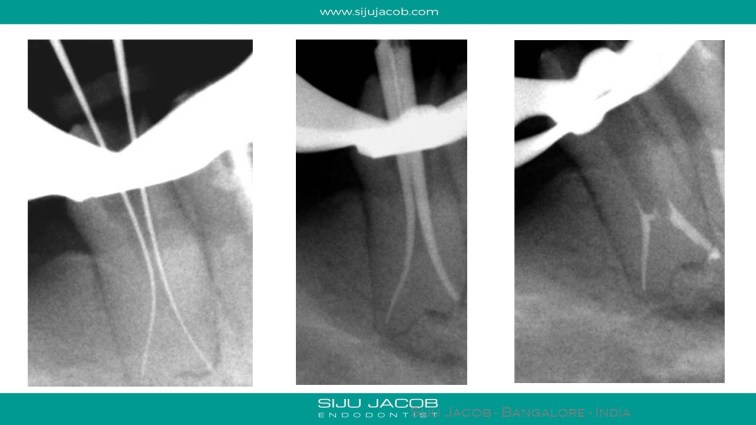

Endo and crowns were done by a general practitioner, after which the patient developed pain and tenderness. I Re-treated both teeth and placed fiber posts to strengthen the hollowed out coronal portion.